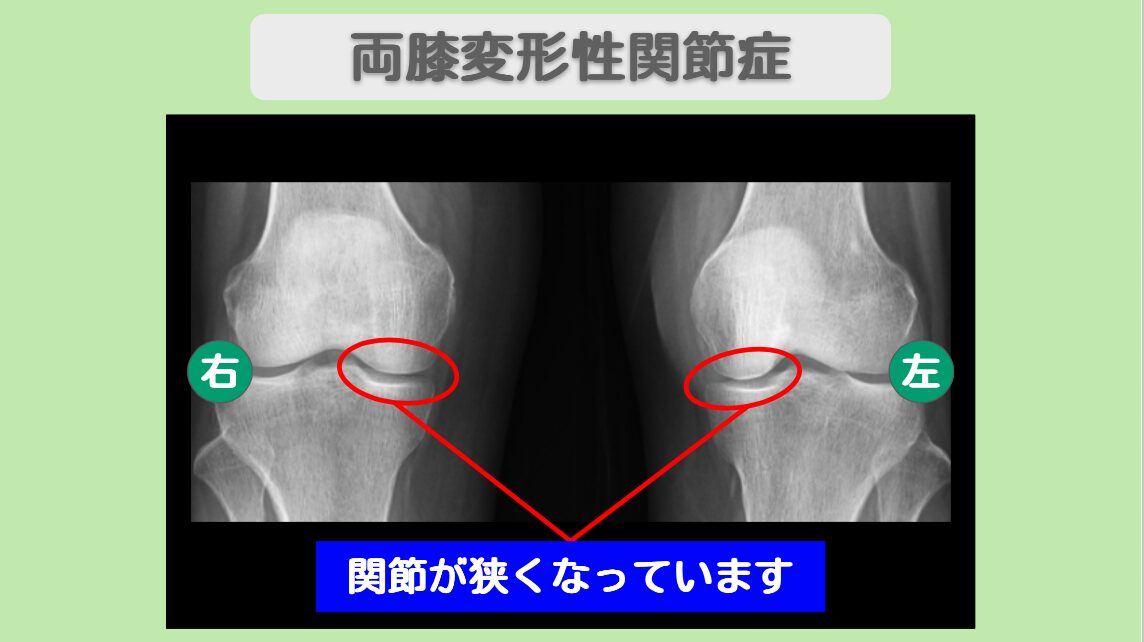

レントゲン所見

この患者様は、10年前からの両膝関節痛のため受診していただきました。当時、近くの整形外科で変形性膝関節症と診断されたそうです。以後、痛み止めを飲みながら過ごしてきましたが、最近では立っていることも辛くなってしまいました。レントゲンを再度撮影すると、軟骨のすり減りが進行しており、医師から人工関節を勧められました。まだまだアクティブな活動を続けたい患者様は人工関節を躊躇し、軟骨を再生させる方法を探され、幹細胞治療に辿り着いて当院を受診されました。